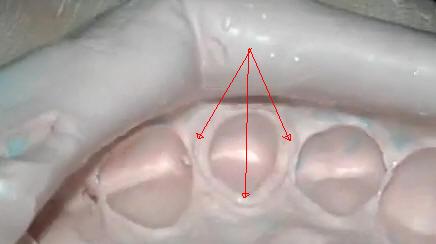

Vista palatina del

tallado |

Ver el hombro realizado

en palatino que debe ser supragingival |